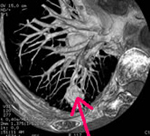

胸部CT

陰になっている部分や小さい病変もよくわかります。

| 胸部CT | 12,100円 | 咳・痰・胸痛など | 肺癌・肺炎・肺気腫など |